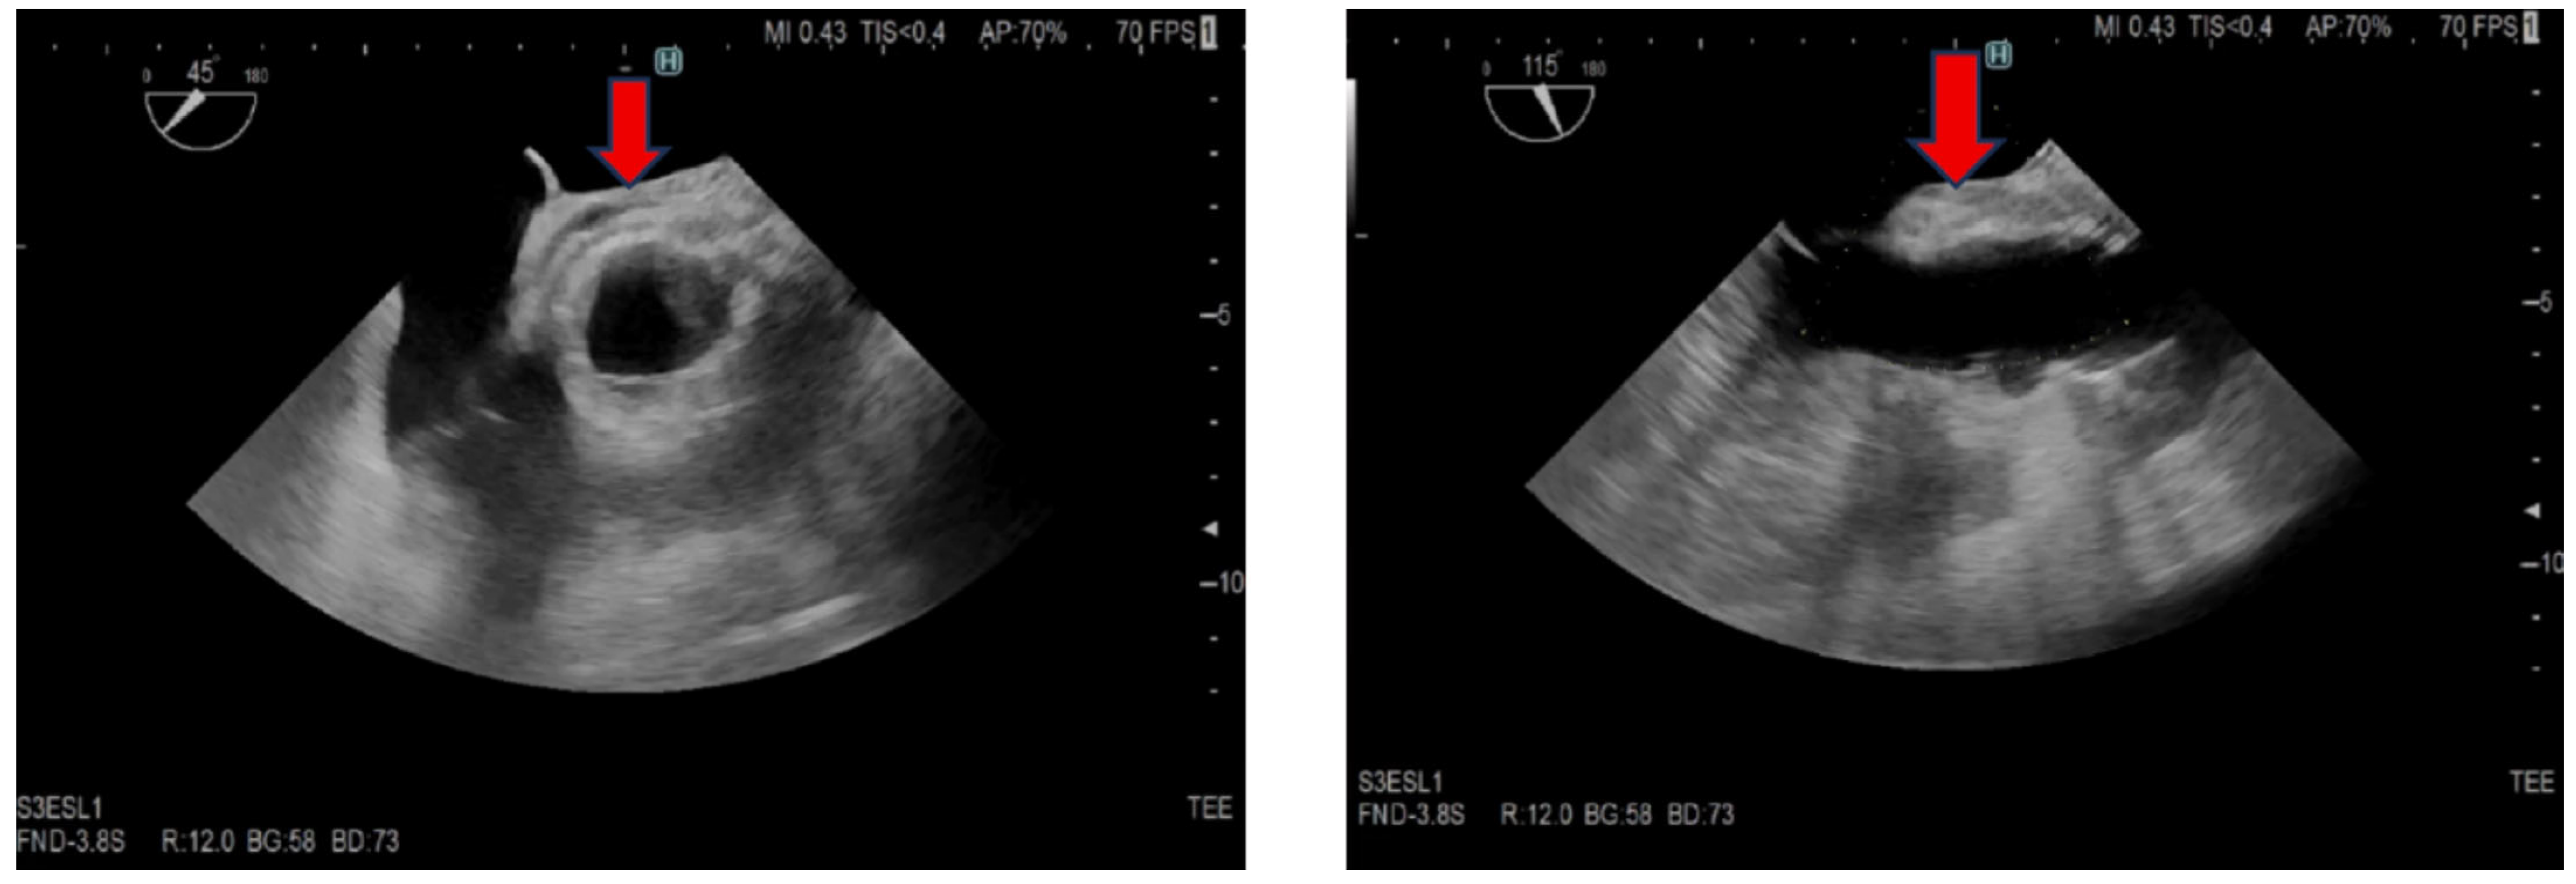

2. Case Presentation